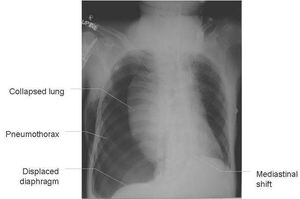

It is a serious type of pneumothorax that can become life threatening condition if left untreated with an imediate care. It results from positive pressure build-up secondary to a flap valve mechanism (or one-way valve) resulting in total lung collapse. There will be also Increased intrathoracic pressure restricts cardiac output that may result in shock and death. Symptoms are unilateral, pleuritic chest pain, breathlessness, respiratory distress, and shock symptoms.This X-Ray shows the radiological findings in case of tension pneumothorax.